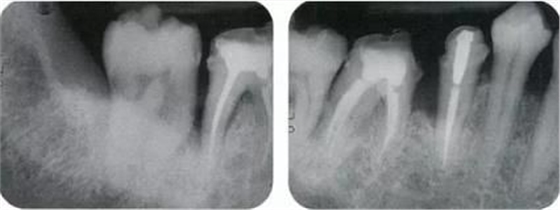

▲圖11-1,2

▲圖11-1,2 術(shù)前的X光片、右下6,7之間存在牙根接近,并存在10mm的牙周袋。